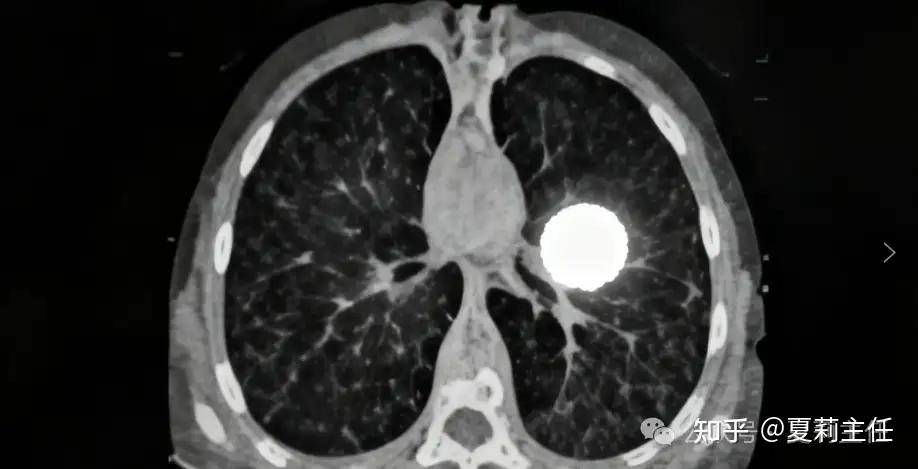

很多人做过肺部CT之后,以为只要检查过一次,就不用太在意了。殊不知,数百名医生强调,做了肺部CT之后,患者其实还有很多地方必须关注。肺部CT虽然能提供非常清楚的肺部影像,但它只是一个工具,解读结果和后